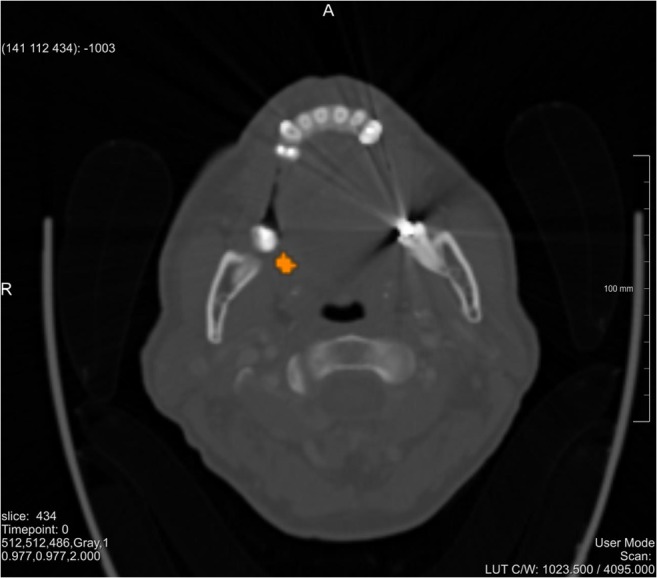

Multiple studies have already been conducted on head and neck tumor segmentation, but due to its high morphological variance, no single segmentation technique was yet capable to segment the complete volume of all tumors [36]. A simple threshold-based segmentation approach was chosen in this exploratory study. The result of the segmentation was qualitatively evaluated by a senior surgeon who judged the degree of accuracy to be clinically acceptable. A relative threshold value of 29.5 was used for the case shown in Fig. 2 (Note, Figs. 2, 3, and 4 belong to the same patient with two tumors. However, Fig. 2 shows an axial slice where only the “upper” one of the two tumors is visible). Further analyses on image segmentation have been considered as out of scope, also due to the limited resolution of the available HMDs.

Fig. 2.

Segmented PET-CT slice of the patient. The tumor is shown in orange, (for interpretation of the references to color in this figure legend, the reader is referred to the web version of the article)